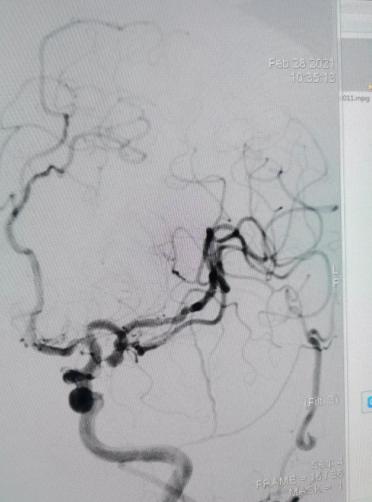

2月28日,景德镇市第三人民医院神经内科、心血管内二科、ICU、麻醉科组成多学科联合手术救治组,为一名七旬患者实施临时起搏器保护下颅内动脉瘤介入栓塞术。

该患者是一位75岁女性,因蛛网膜下腔出血从抚州地区转入市三院神经内科。该患者既往有阵发性室上速病史,入院CTA提示左侧大脑中动脉动脉瘤,需行颅内动脉瘤介入栓塞术。患者手术全麻后心率过山车,快时达130次每分,慢时只有30至40次每分,情况危急,为确保手术安全进行,麻醉科张丽副主任医师药物积极控制,同时卒中中心主任王新立即组织专家团队进行抢救,心血管内二科主任华永平和ICU主任曾满生迅速参与救治,果敢告知家属后,于左侧股静脉穿刺置入临时起搏器,维持心率70次每分,生命体征稳定后,王新主任快速栓塞左侧大脑中动脉破裂动脉瘤。术后,该患者在ICU迅速得到复苏,神志清楚,四肢活动正常,生命体稳平稳,次日转入普通病房。